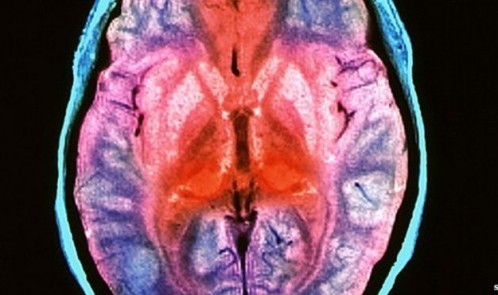

در حال حاضر این بیماری درمان پذیر نیست و در کمتر از یک سال از شروع علائم به مرگ منتهی می شود. کالبد شکافی این بیماران، ایجاد حفرات در مغز و اسفنجی شدن آن را نشان می دهد.